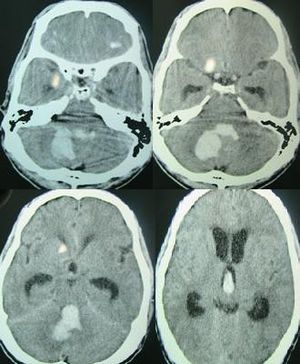

يتم التعرف على النزف الدماغي عن طريق التصوير المقطعي المحوسب حيث تظهر الدماء أكثر أفتح عن الأنسجة ويفصلها عن الجدار الداخلي للجمجمة نسيج الدماغ. الأنسجة المحيطة بالدماء عادة ما تكون أقل كثافة عن بقية الدماغ بسبب الوذمة، ومن ثم فيظهر أفتح في التصوير المطقعي المحوسب.